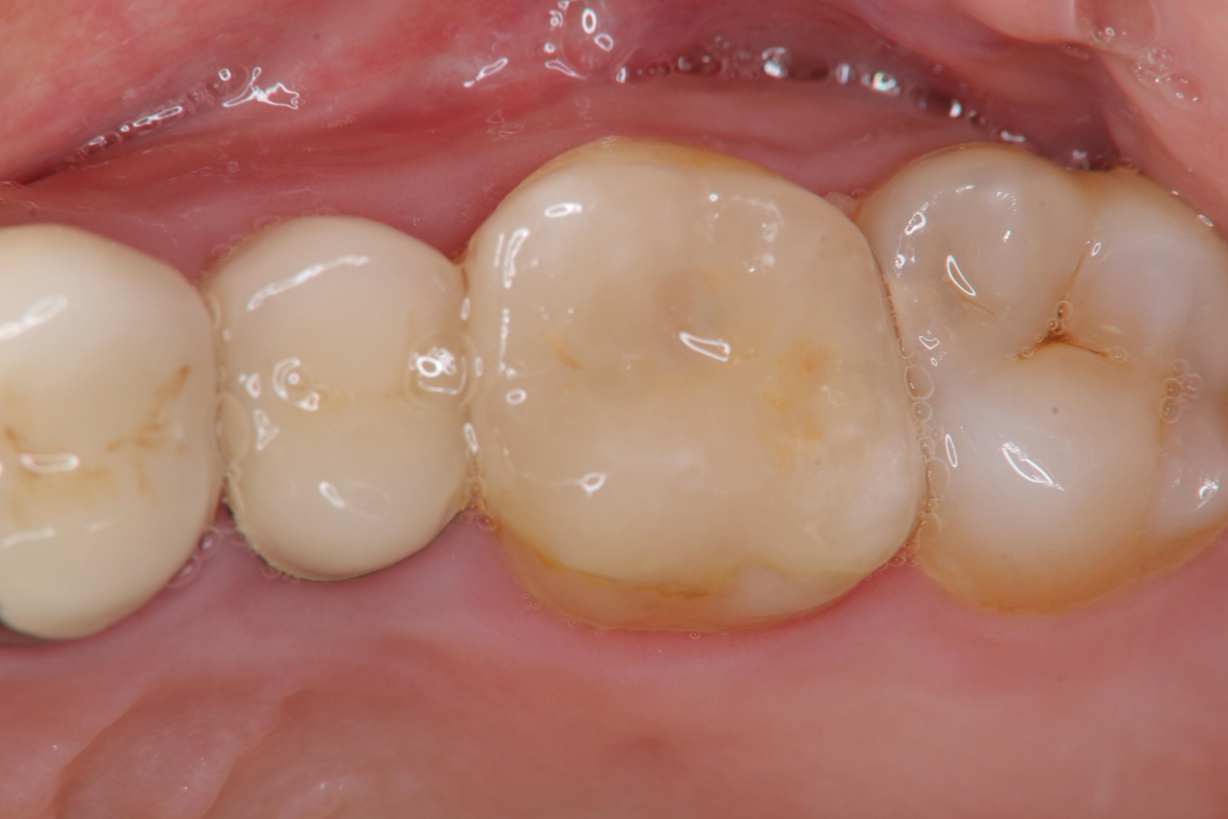

陶瓷冠塊體口內黏著

治療後口內照